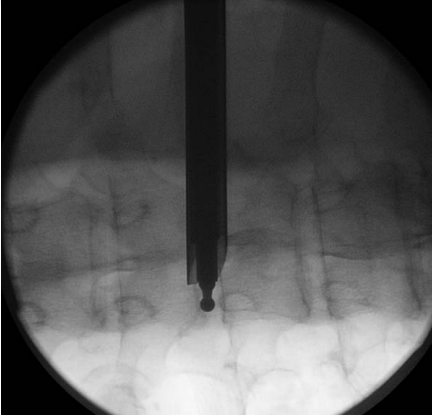

4.作7mm皮肤切口,触摸T1椎体前缘,插入克氏针后置入环钻,方向为从前上到T1-2的后方。

环钻上骨质,使用c臂确认工作套管位置